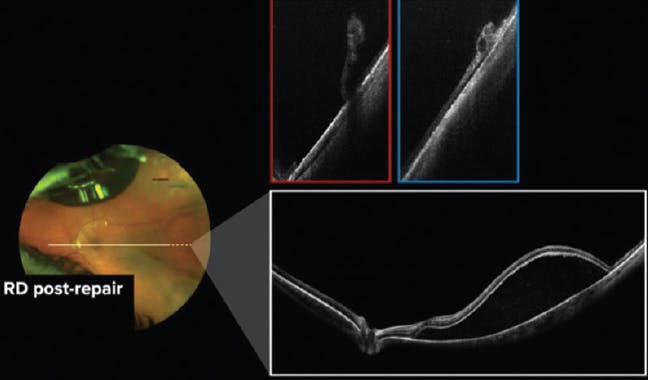

A 57-year-old White woman was referred for a retinal detachment with BCVA of 20/200 in the left eye. Peripheral OCT revealed no other retinal breaks or tears, and pneumatic retinopexy was performed. During the follow-up period, peripheral OCT allowed us to track the resolution of subretinal fluid and monitor healing (Figure 3).

<p>Figure 3. Peripheral OCT allowed visualization of subretinal fluid during follow-up of a patient who underwent pneumatic retinopexy for a retinal detachment.</p>

Figure 3. Peripheral OCT allowed visualization of subretinal fluid during follow-up of a patient who underwent pneumatic retinopexy for a retinal detachment.

In our experience, retinal tears addressed by pneumatic retinopexy may not resolve in the presence of undetected retinal tears or holes. In this case, the surgeon was able to execute treatment with the confidence that no other pathology was present and observe the patient during follow-up using peripheral OCT.